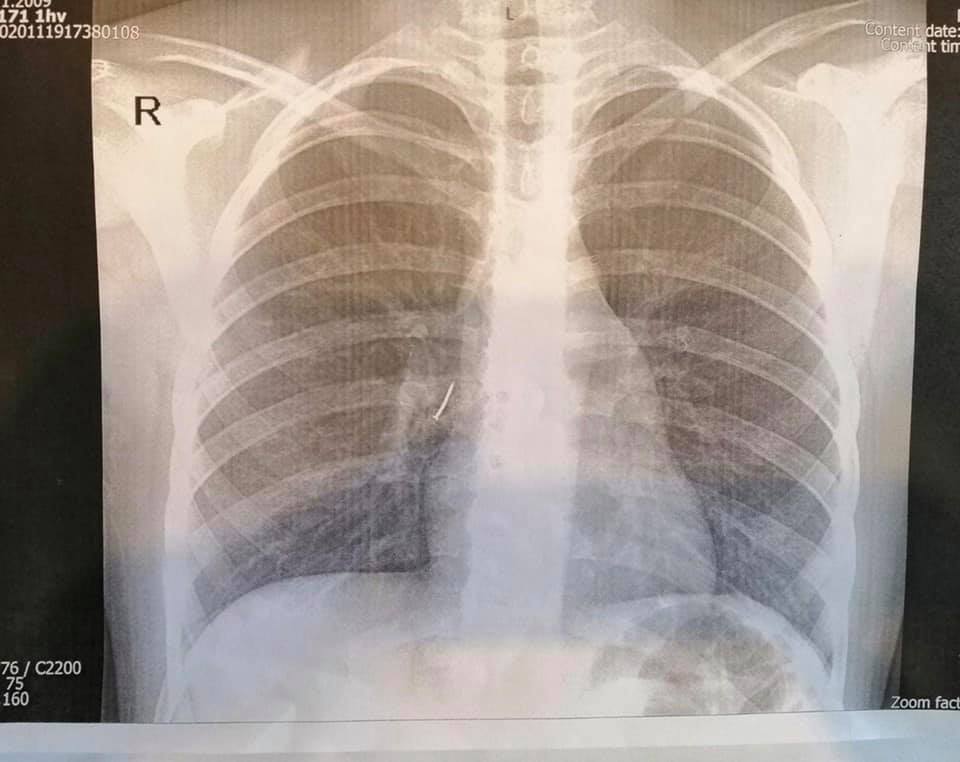

21 листопада хірурги Львівської обласної дитячої лікарні ОХМАТДИТ прооперували 11-річну дівчину з Жидачівського району, яка вдихнула канцелярський цвях. Читайте всі новини Львова за сьогодні.

Стороннє тіло потрапило у бронху, тож дівчинку терміново прооперували. Втручання проводив дитячий хірург Олександр Колодій, у його практиці це третій випадок, коли дитина ковтнула цвях.

«Ми виконали ригідну трахеобронхоскопію під наркозом. Спеціальними ендоскопічними інструментами - щипцями під оптичним контролем - з правого проміжного бронха дитини ми дістали канцелярський цвях з пластмасовою частиною і гострим вістрям. То було непросто, адже пластмасова частина цвяха повністю перекрила бронх так, що нижня доля правої легені майже не функціонувала», - розповів хірург.